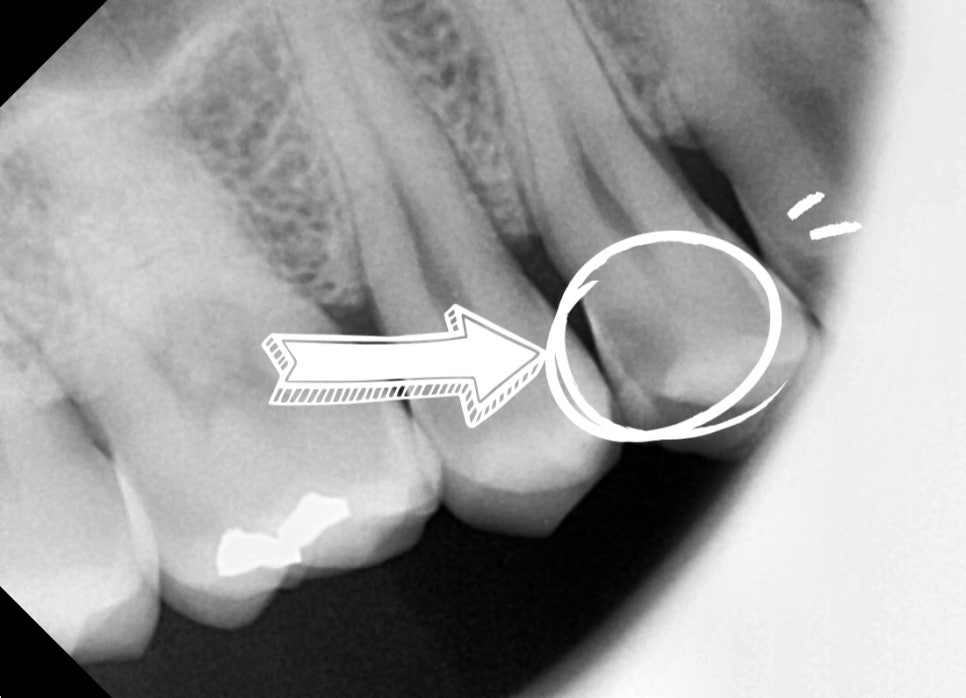

치과에서 찍은 사진과 엑스레이를 확인해보니,

깨진 틈으로 세균이 들어가

신경이 이미 많이 손상된 상태였습니다.

이대로 두면 통증이 점점 심해지고,

결국 발치하고 임플란트를 해야

하는 상황까지 갈 수 있기 때문에

바로 신경치료가 필요하다는 설명을 드렸습니다.